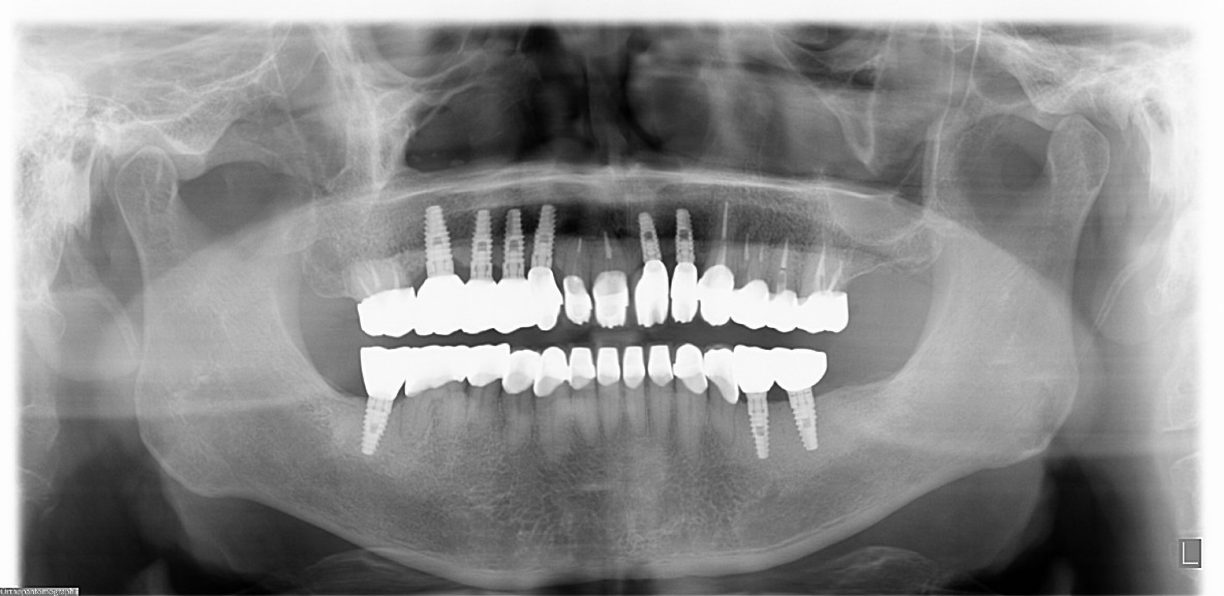

| 主訴 | 歯がグラグラで噛むことができない。インプラントをして欲しい。 |

| 治療内容 | 歯周病で骨の吸収が重度で保存不能なため抜歯、仮の入れ歯を作り、6ヶ月の抜歯窩の治療の後に、インプラントのCTによる診査診断を行い、下顎に6本インプラント埋入と同時に仮歯を入れる。その後、上顎は8本のインプラント埋入と同時に仮歯を入れる。左右上6はソケットリフトによる上顎洞拳上術を行う。その後免荷期間6ヶ月待ってセラミックを用いた上部構造作製、装着しメンテナンスに移行する。 |

| 治療費 | 9,000,000円(税込) |

| 治療期間 | 2年3ヶ月 |

| 治療回数 | 90回 |

| 想定されたリスク | 重度の歯周病により無歯顎になったため、プラークコントロール不良による、術後のインプラント周囲炎が懸念される。歯冠の部分はセラミックなため欠ける可能性がある。 |